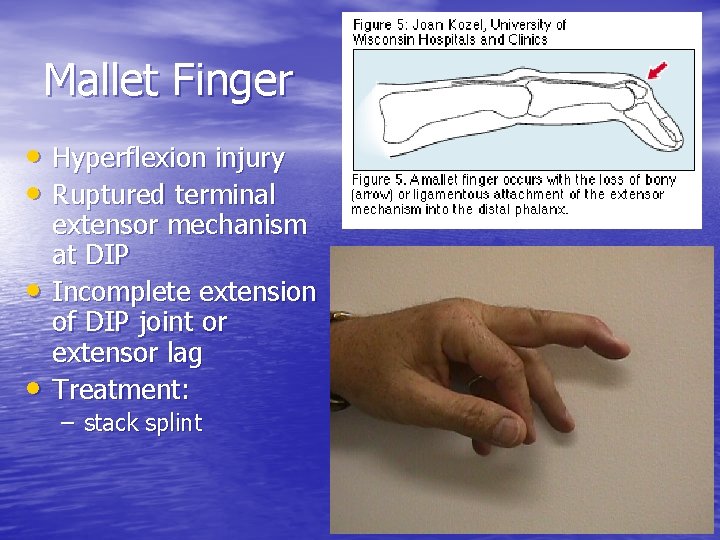

Mallet Finger • Hyperflexion injury • Ruptured terminal • • extensor mechanism at DIP Incomplete extension of DIP joint or extensor lag Treatment: – stack splint